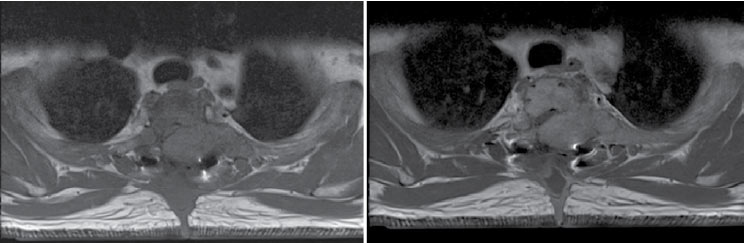

Dentro de los casos reportados, es usual que se realizaran múltiples estudios para enfocar la lesión entre los cuales se encuentran: radiografías en las que se observan lesiones líticas únicas o múltiples mal demarcadas en expansión, además de desmineralización generalizada. Por otro lado, la tomografía muestra mejor definición de la erosión local y extensión presentada no solo en hueso sino también en tejido blando, que se intensifica con el medio de contraste; sin embargo, no es específica para diagnosticar este tipo de tumores, porque no los distingue de otro tipo de lesiones. Por último, la Resonancia Magnética es de gran ayuda en la mejor caracterización de las lesiones y su extensión, éstas se ven usualmente hipointensas en la secuencia de T1, hiper o hipointensas en la secuencia de T2 (esto se lo debe al grado de su componente quístico), con realce posterior a la administración del medio de contraste por su alta vascularización, la formación de hemorragias intratumorales que generan niveles líquido-líquido. El compromiso en columna se caracteriza por ser de componente sólido, que frecuentemente causa destrucción de la corteza y extensión a tejidos blandos (figuras 1 al 4)(5).

| Figura 2. Secuencia T1: imagen de la derecha sin contraste, imagen de la izquierda con contraste. Nótese cómo la masa se realza con medio de contraste, lo que evidencia interrupción de la membrana basal |